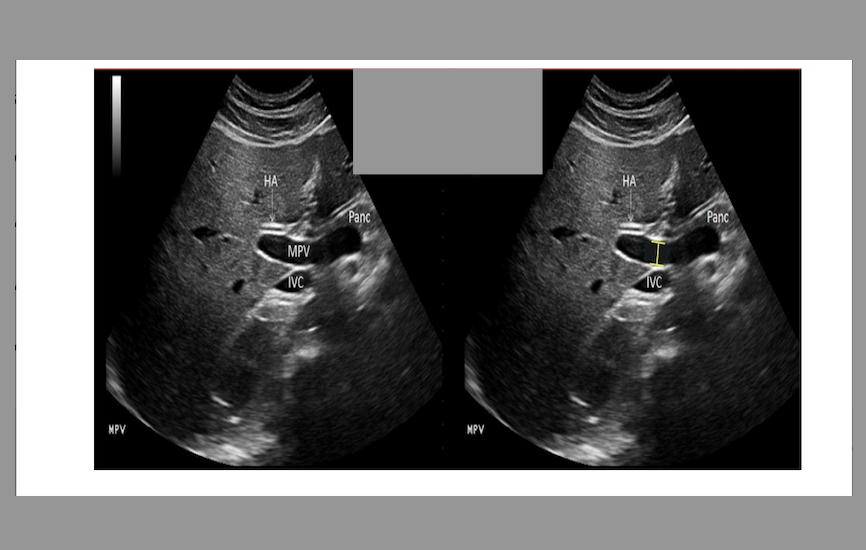

this image is

.

a) incorrect label + diameter

b) correct label; incorrect diameter

c) correct label; correct diameter

d) incorrect label; correct diameter

a. incorrect label + diameter